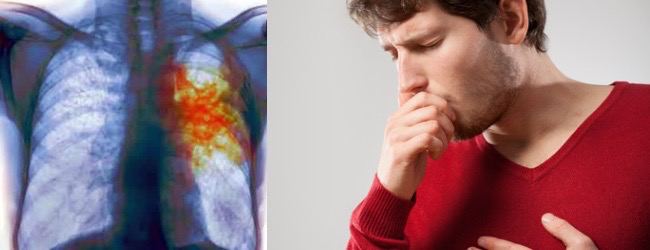

Симптомы туберкулеза: Как распознать и что делать

Раздел: Визуальные уроки